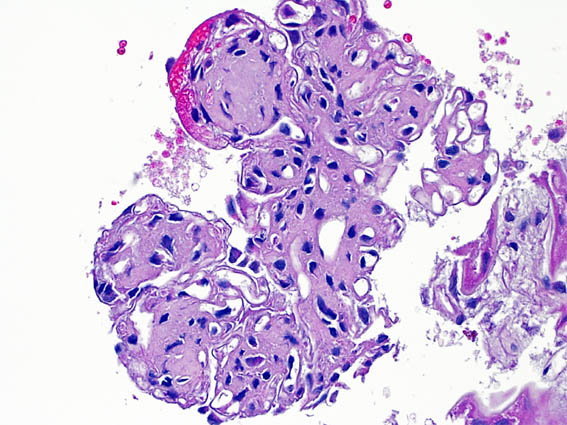

Figura 1.

H&E, X200.